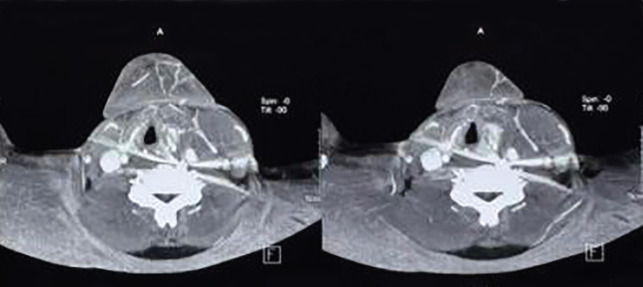

Airgun injuries are prevalent in the pediatric population. The present study described a case of air gun pellet injury to the left carotid artery and its successful management. A 25-year-old man presented to the emergency department complaining that his son had accidentally injured him with an air gun pellet while playing. The X-ray cervical spine revealed a single foreign body (pellet) located directly anterior to the C5-C6 vertebra. A CT angiography of the neck showed a spherical hyperdense object just anterior to the C6 vertebral body on the left side, 3 mm posteromedial to the left common carotid artery, which was most likely a pellet foreign body. The patient was sent to operation theatre (OT) for exploration. There was a rent in the internal carotid artery with active bleeding. After exerting both proximal and distal control, the rent was closed. Close air gun injury could result in gunshot wounds, as in the present case. Plain X-rays in AP and lateral view are required. Nonoperative management could be employed in a restricted group of patients with satisfactory outcomes. Those who have vascular involvement will require surgical intervention.